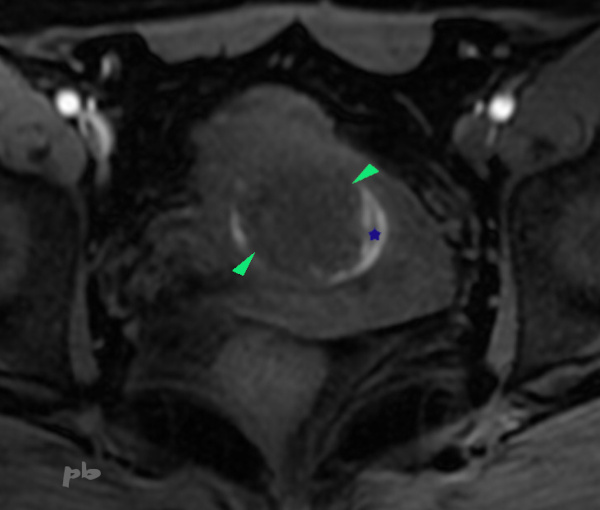

IRM – Coupe axiale T1.

Hypersignal T1 arciforme (★) moulant le polype (►) : sang.

La chirurgie et l’anapath ont permis de confirmer l’absence de malignité (leiomyome).

Pour d’autres images de cette patiente, voir chapitre « Exploration d’un endomètre épais » images 14.